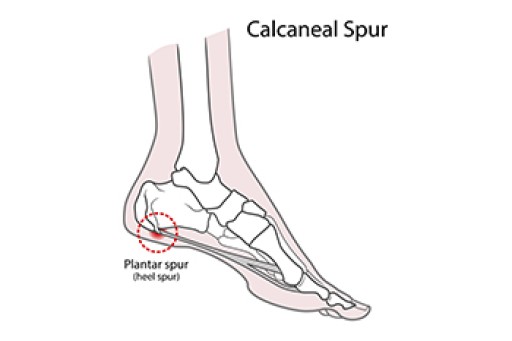

Kenali apa itu Heel Spur dan cara cara merawatnya discount, Dr Zubaidi Hj Ahmad SAKIT TUMIT HEEL SPUR Heel Spur atau calcaneal spur ialah keadaan yang disebabkan oleh pemendakan kalsium tidak normal sehingga mengakibatkan berlakunya benjolan tulang di bahagian... discount, Armels Academy APA ITU HEEL SPUR Heel Spur adalah. Facebook discount, Heel Spur Punca Simptom dan Rawatan The Diagnosa discount, 104KB 2001 null null null null null null null 1 2003 null gdUFSGid890e3M discount, Heel spur discount, Two Places Where Heel Spurs Can Form Blog discount, Heel Spurs Treatment Podiatrist Foot Doctor Punta Gorda FL 33950 and Port Charlotte FL 33952 discount, Heel Spur Causes Management Singapore Straits Podiatry discount, Foot Pain Treatment Without Injections Or Surgery discount, Plantar Fasciitis Heel Pain Stratagies to relieve pain discount, Causes and Risks of Heel Spurs Blog discount, The Definition of a Heel Spur discount, Heel Spurs Causes Symptoms and Treatment discount, Homeopathic Treatment For Heel Spur discount, Treating Bone Spurs discount, What Is a Bruised Heel discount, Bone Spurs Foot and Ankle Clinic DRHC Dubai discount, Plantar calcaneal spurs in older people longitudinal traction or vertical compression Journal of Foot and Ankle Research Full Text discount, Calcaneal Spurs Physiopedia discount, Heel Spur Taping discount, What Is a Heel Spur discount, AR Fisioterapi Apakah itu BONE SPUR Bone. Facebook discount, Painful Heel Spur Management in Singapore Podiatry Clinic discount, Plantarfasciitis What the Heel discount, Penyelesaian Heel Spur 5 Cara Iswanah Fisioterapi Atasi Iswanah Physiotheraphy discount, Heel Spur Treatment Relief The Foot Practice Singapore discount, Heel Pain Spur Pain aka Plantar Fasciitis My Bowen Therapy discount, What is Heel Spur and how to correct it relieve your pain discount, Calcaneal Spurs Physiopedia discount, Heel Pain Causes Best Treatment Options In Malaysia discount, Tumit Spur Punca Pengurusan Singapura Straits Podiatry discount, Plantar Fasciitis Home Consultant Orthopaedic Surgeon discount, Heel Spur or Calcaneal Spur discount, Iswanah Shah Alam APA ITU HEEL SPURS Plantar fasciitis Plantar fasciitis adalah keadaan di mana tisu plantar fascia yang menghubungkan tulang tumit. Instagram discount.